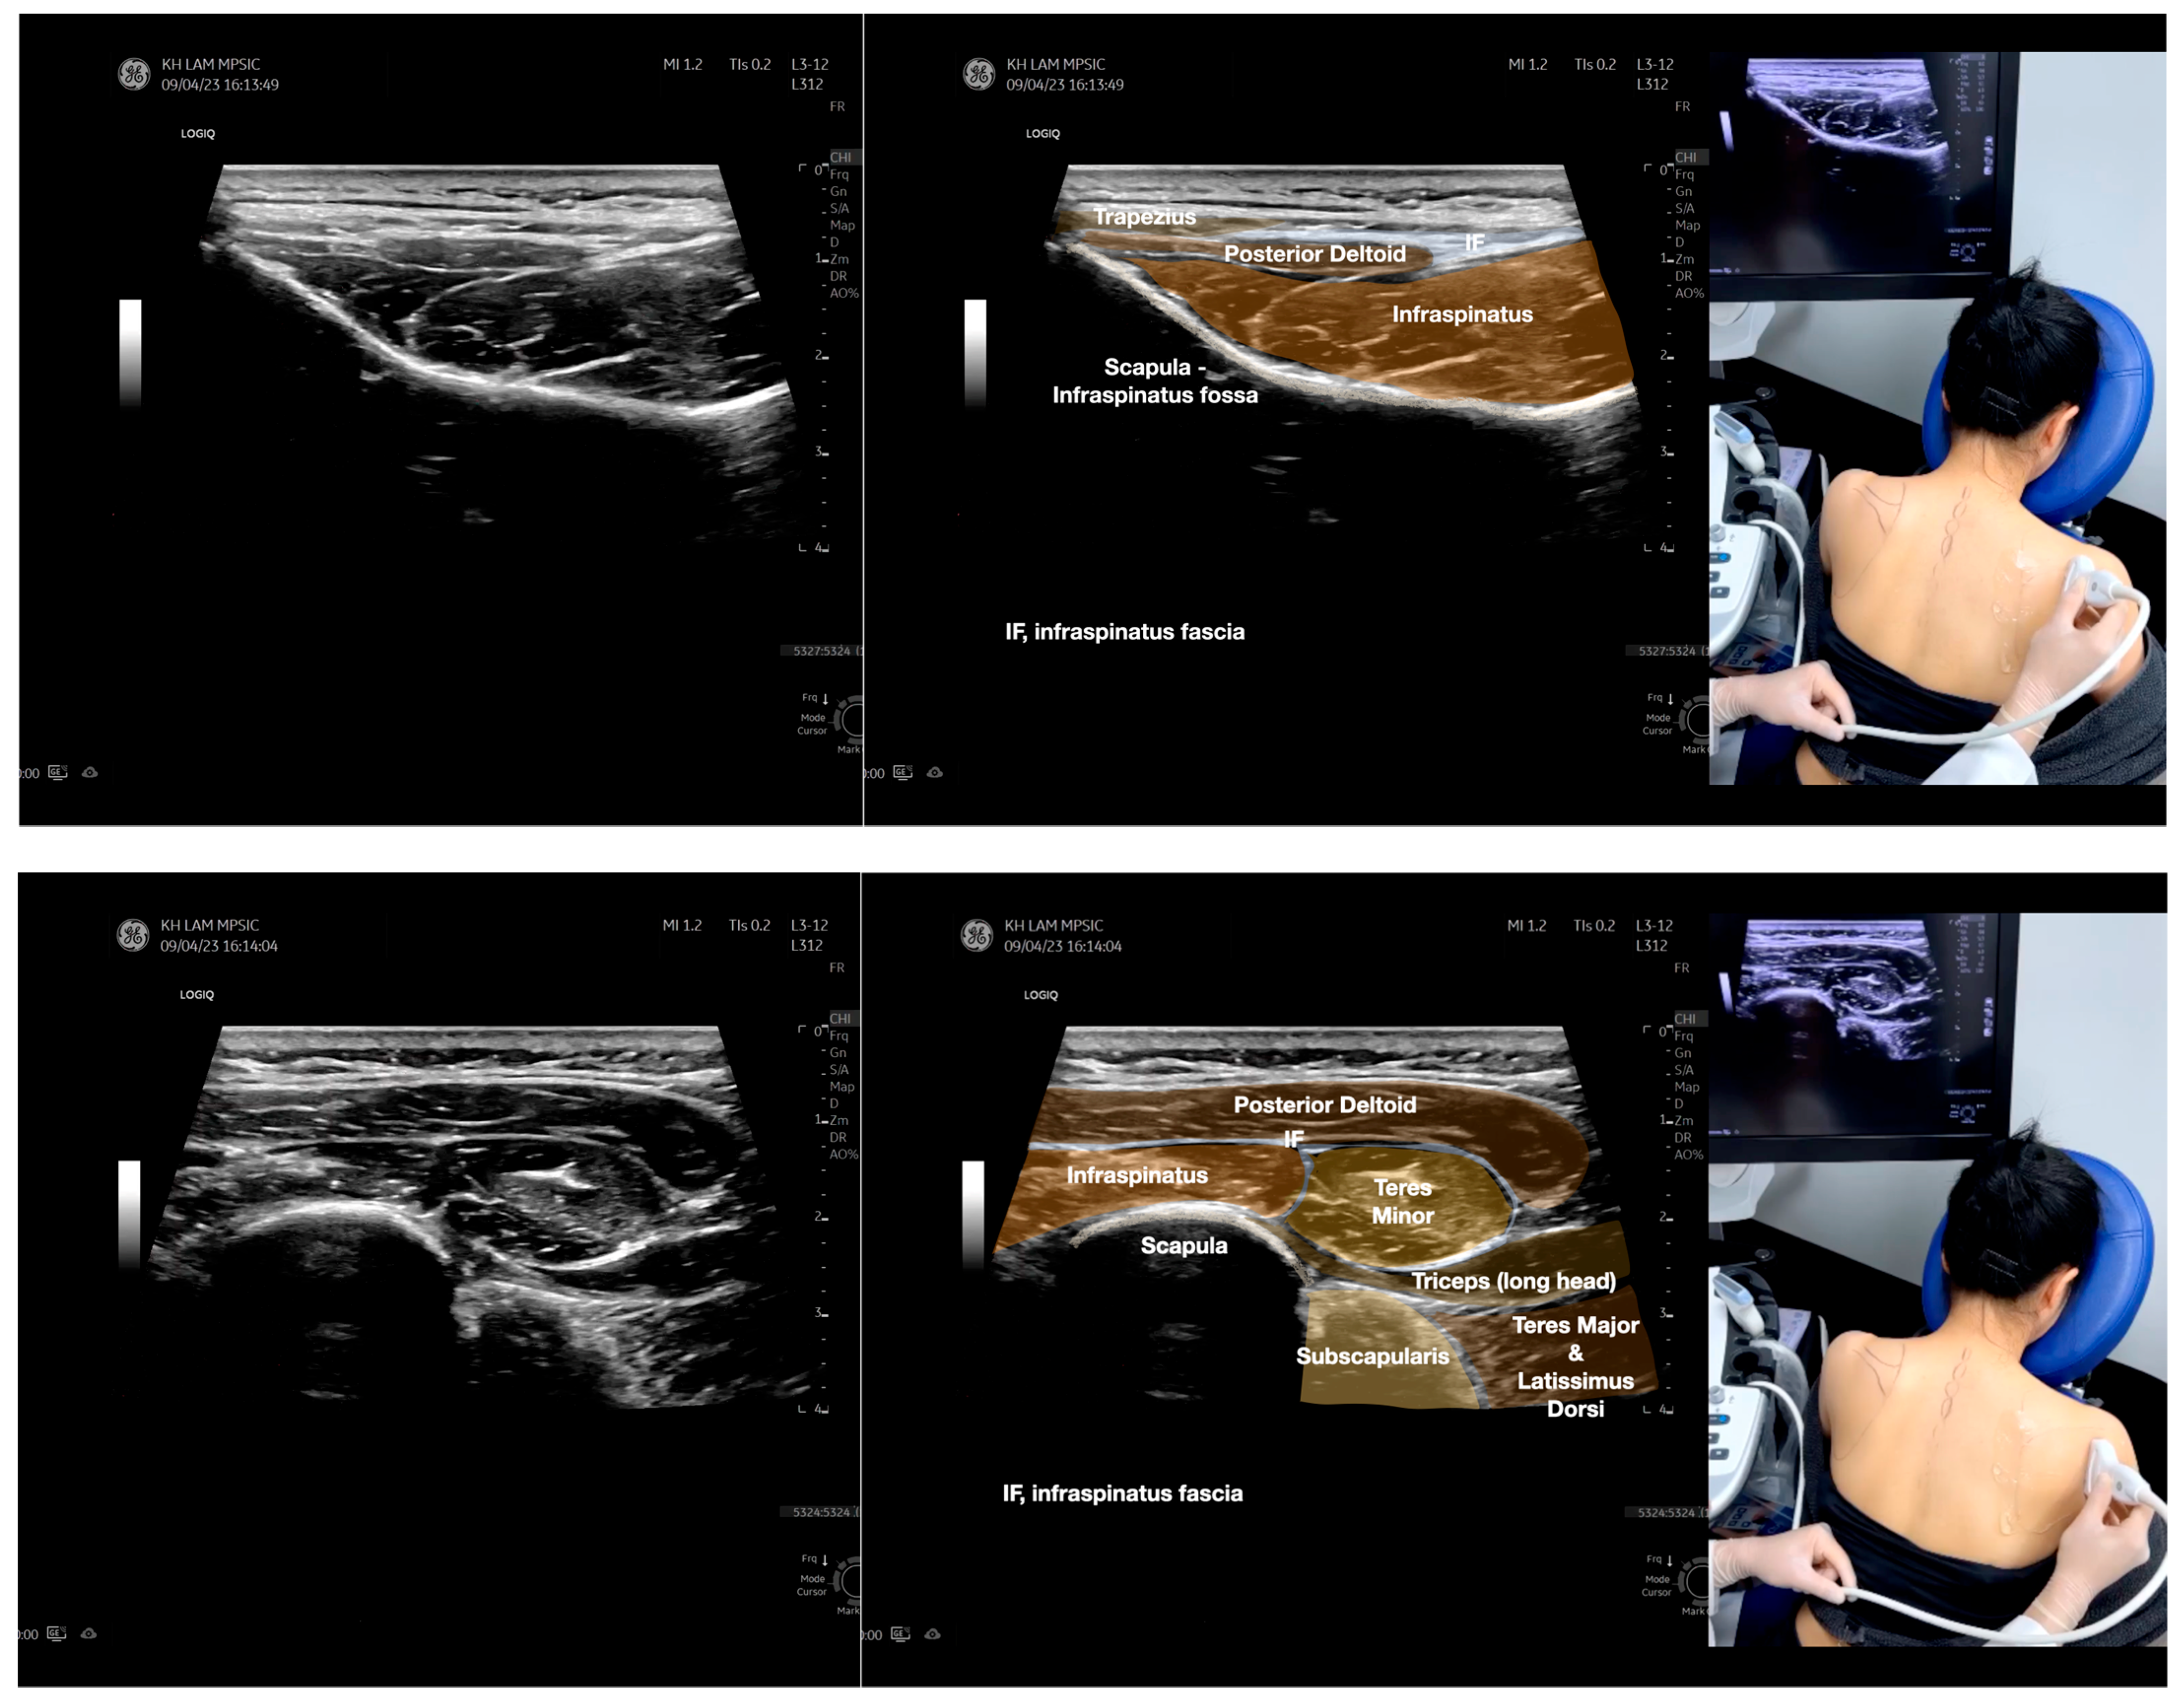

Figure 2.

Sonoanatomy of the lateral border of the inferior trapezius, its related muscles, and the infraspinatus fascia. The step-by-step scanning techniques of the structures illustrated in this figure have been shown in Video S6. Available online: https://www.dropbox.com/s/vjj49wiwdsidouz/Figure%202.docx?dl=0 (accessed on 1 January 2023). Dynamic ultrasound scanning of the anterior shoulder with the humerus externally rotated (palm up), elbow straight, and the shoulder actively flexed and abducted at about 90 to 100 degrees shows that the fibrotic and thickened bursa was noted to be snapping between the subscapularis tendon and the coracoacromial ligament, as shown in Video S3. The patient noticed this snapping during many of his daily activities with his shoulder flexed just above 90 degrees, e.g., taking off clothes and combing hair. Ultrasound-guided injection of the thickened and fibrotic bursa did not reproduce the usual pain nor reduce the pain, and it did not improve the shoulder snapping and flexion power with the elbow straight, shoulder flexed to 90°, and the humerus externally rotated (palm up). Ultrasound-guided injection of the cortical break reproduced the concordant pain and temporarily and partially reduced the pain with snapping and residual anterior shoulder pain (Video S4), but it did not change the snapping or weakness in the right shoulder flexion with the humerus in external rotation. With the failure of direct anterior treatment to the suspected lesions, it was essential to further explore other causes for the anterior painful snapping. Further detailed musculoskeletal examination of the scapular movement showed that the right scapulothoracic movements were not smooth compared to the left counterpart (Video S5) [4,5]. There might be some disruptions in the right infraspinatus fascia (IF) and its related muscles, including the lateral edge of the right inferior trapezius, rhomboid minor and major [6], teres major, latissimus dorsi [7,8] (LD), and posterior deltoid attachments to the IF [9,10]. Clinically, prominent and active trigger points were observed in the right infraspinatus muscle. Holding the inferior angle of the scapula, with the examiner’s fingers, especially over the origin of the teres major muscle over the scapula, the latissimus dorsi [11,12,13] and the scapular insertion of the rhomboid major muscle significantly improved the power of the resisted shoulder flexion with the elbow straight and the shoulder flexed to 90° with the humerus externally rotated (palm up). In order to illustrate the utilization of ultrasound-guided sonopalpation and ultrasound-guided digital palpation for detecting the suspected lesions of the IF and its related muscles, we presented the following videos (Videos S6–S9) and still images (Figure 2, Figure 3, Figure 4 and Figure 5) to demonstrate the essential techniques and crucial points of getting the normal sonoanatomy of the IF and its related structures. The gross anatomy of the IF and its related muscles were also shown in Figure 6, Figure 7 and Figure 8.